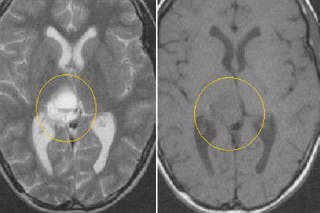

Для визуального восприятия✨

Сегодня разберем по каким 7 признакам понять, что шишковидная железа (эпифиз) “спит” — чтобы вы могли честно посмотреть,...